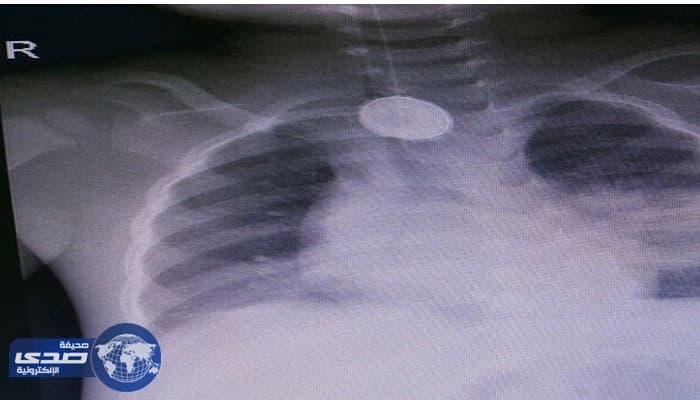

وفي تفاصيل الحدث اوضحت وزارة الصحة انه قد تم تحويل الطفل لمستشفى الولادة والأطفال اثر معاناته من كتمه وصعوبة في التنفس وارتفاع في درجة الحرارة كما تم اجراء الفحوصات المطلوبة للطفل والذي تبين من خلالها وجود بطارية حارقة اسفل الرقبة.

كما اضافت وزارة الصحة ان الطفل ادخل مباشرة على العمليات بمستشفى الولادة والأطفال بمكة المكرمة حيث تم اجراء عملية جراحية وتم بحمد الله استخراج البطارية التي كانت منغمسة بجدار المريء وجدار القصبة الهوائية.